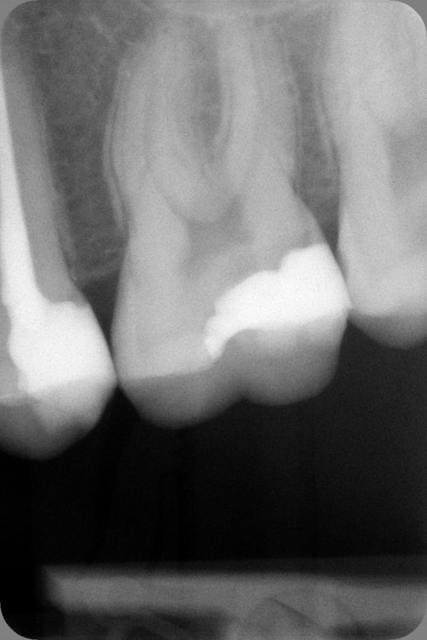

Tiens pour rigoler un peu, je poste une radio pour savoir ce que feraient les uns et les autres sur cette 26 et cette 27.

La réponse des étudiants m'intéresse tout particulièrement.

> Tiens pour rigoler un peu, je poste une radio pour savoir ce que feraient les

> uns et les autres sur cette 26 et cette 27.

> La réponse des étudiants m'intéresse tout particulièrement.

26 : si la limite est remontable au compo : onlay, sinon cr sur dent vivante

27 : compo

Désolé mais je ne sais pas faire de plan de traitement systématique sur la base d'une seule rx. la 26 peut très vite tourner en endo . souvent on a un bon tiers de tissu carieux supplementaire à ce qui est attendu à la rx.

Je previens le patient que je curette et en fonction de l'etendu des degats on avise mais que plusieurs options seront possibles.

Bon d'après la radio il n'y a pas urgence ca peut être remis à plus tard, c'est que j'ai un de ces planning blindé moi ............)))))))))

Disons 2 amalgames si j'ai de la place.)))))))

Et pour le volume de la 26, manque de bol pour mon portefeuille, en vrai c'était pas si profond. Je me referai sur la 24 à couronner (bah oui je vais pas laisser un composite 3 faces quand même, cochon de dentiste).

Reste la 7, on verra.

On ne t'a pas dit ? Les composites, ça ne marche pas !

D'abord endo 26 et 27, pas trop près des apex, parce qu'après ça fait des "arthrites".

Ensuite on fait deux couronnes, parce que pour des dents dévitalisées, c'est bien le minimum.

Et puis on n'oublie pas de faire la place pour deux beaux inlay-core, parce que pour faire des couronnes c'est bien le minimum !